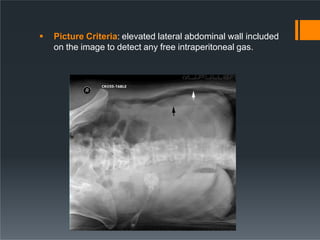

ď‚§ Picture Criteria: elevated lateral abdominal wall included

on the image to detect any free intraperitoneal gas.

Lateral Decubitus ď‚§ Performedas an alternative to the PA erect view to assess for free gas in the abdominal cavity if the patient is unable to sit or stand. ď‚§ POSITION of the patient: I. Patient in lateral recumbent position II. Elbows and arms flexed and hands resting near head III. Cassette positioned in vertical bucky against the posterior aspect of the trunk. IV. Central ray is directed perpendicular to the midpoint at the level of iliac crest with x-ray tube horizontally

ď‚§ Picture Criteria:elevated lateral abdominal wall included on the image to detect any free intraperitoneal gas.